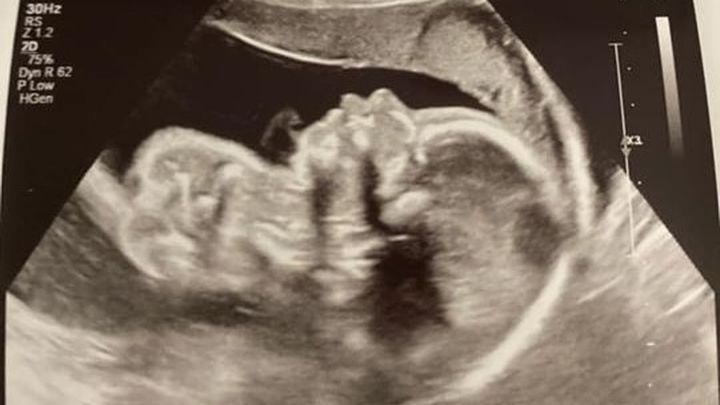

Katie & Corey Loehr- On April 7th my husband and I were on our way to our anatomy ultrasound, we were super excited to verify the gender and to see a detailed scan of our baby. All I can remember was being on cloud nine while looking at the ultrasound smiling from ear to ear in excitement. We got our ultrasound pictures of our sweet baby boy!! He was so tiny and perfect in every way, we kept laughing about how he was not shy to show off that he was a boy. The ultrasound tech left and said the doctor will be in to see you shortly, we were still talking about the pictures and his cute little hands and feet. Then the doctor walked in and said she wanted to double check the ultrasound tech; I didn’t think anything of it because I was just excited, I get another chance to see my baby. After about fifteen minutes the doctor told us she sees and abnormality with his heart. At this point my heart sank into my chest and the whole room got quiet. It felt as if the room had stopped for the rest of the ultrasound. She showed us a diagram of what a normal heart looks like and then showed us how underdeveloped one side of his heart was (Hypoplastic Left Heart Syndrome). Trying my best to listen through all the shock and tears she explained that his heart and stomach were also on the wrong side of his body, she said this was called Heterotaxy. At this point she told us she wanted to schedule an appointment with a pediatric cardiologist to verify and explain more. I just remember sitting in the car and my husband and I not saying a word the whole way home. Thoughts were racing. Is there anything I have done to cause this? Did I do something before I knew I was pregnant? Can I change the diagnoses? What is the outcome? Will my baby be okay? We had to wait about a month for him to get a little bit bigger before seeing the cardiologist, that was the longest month of our lives. After meeting with this specialist from Riley she did verify that he has HLHS and Hetrotaxy. Hypoplastic left heart syndrome (HLHS) is a congenital birth defect that affects the left side of the heart, leaving it under-developed and unable to pump oxygenated blood through the body. The left ventricle of the heart is too small in patients with HLHS, leaving the right ventricle to do all the work. HLHS typically requires three reconstructive surgeries to redirect the blood flow: the Norwood (which he will have 4 to 10 days after he is born), Glenn (he will have when he is 3 to 6 months old) and Fontan procedures (which he will have when he is 3 to 5 years old). One of the rarest and more severe heart defects is hypoplastic left heart syndrome (HLHS), which affects about 2 to 3 percent of babies born with a congenital heart defect. Heterotaxy syndrome is a condition in which some of the organs of the body are not located in their correct positions and some organs have not formed normally. Some children with heterotaxy syndrome have complicated congenital heart disease and need heart surgery. Some need abdominal surgery, and some do not have a spleen. Soon after we found out about his condition, we began our journey of multiple appointments, and stressful nights. I am Currently 31 weeks pregnant and we have had our ups and downs between me being sick and small complications during this pregnancy. He is being monitored very closely by some amazing doctors. We have met with a fantastic team up at Riley and are very hopeful of the outcome. I will be induced September 1st and then he will have his first open heart surgery 4 to 10 days after he is born. He will have a total of three surgeries, each surgery will repair his heart a little more. He will be in the intensive care unit for up to 6 weeks after his surgery hopefully less. Currently, he is super active and likes to kick mom all day and especially at night! We are excited to meet our bundle of joy; we have a long road ahead and ask for as many prayers as we can get!